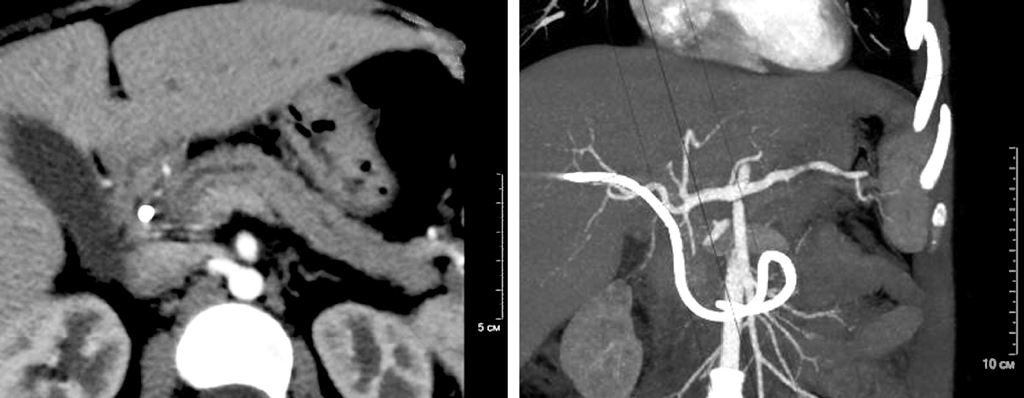

Аутоиммунный панкреатит — особая, своеобразная и относительно новая форма хронического панкреатита, которую в последние годы интенсивно изучают панкреатологи всего мира. Аутоиммунный панкреатит не имеет свойственной только ему клинической картины. Это состояние было впервые описано у взрослых и часто имитирует рак поджелудочной железы. Может поражать несколько органов, синхронно или метахронно, и редко встречается у детей. Представляет собой системное фибровоспалительное состояние с неясным патофизиологическим механизмом, влияющее на различные части тела. При отсутствии лечения заболевание может привести к фиброзу и необратимому повреждению органов, однако сочетание присущих аутоиммунному панкреатиту серологических, гистологических признаков и данных инструментальных методов исследования позволяет установить его наличие. IgG4-ассоциированное заболевание в основном описано у взрослых, поэтому педиатры обычно мало знают о нем. Мы подчеркиваем сложность диагностики аутоиммунного панкреатита — заболевания, связанного с IgG4, у детей. В статье представлены два клинических случая с детьми, которым был диагностирован аутоиммунный панкреатит. У обоих детей наблюдались симптомы абдоминальной боли и/или механической желтухи в сочетании с очаговым увеличением поджелудочной железы, неровностями основного протока поджелудочной железы и дистальным сужением. Согласно нашим данным, диагноз аутоиммунного панкреатита у детей может быть установлен на основе комбинации конкретных клинических симптомов при поступлении и различных результатов визуализации. Своевременно поставленный диагноз и начатое лечение является благоприятным прогнозом для дальнейшего течения данного заболевания и развития осложнений.